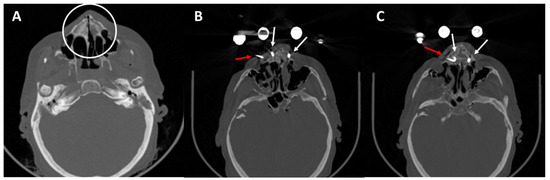

3.4. Postoperative Results in the CT Scans

4.2. Post-Operative CT Scans